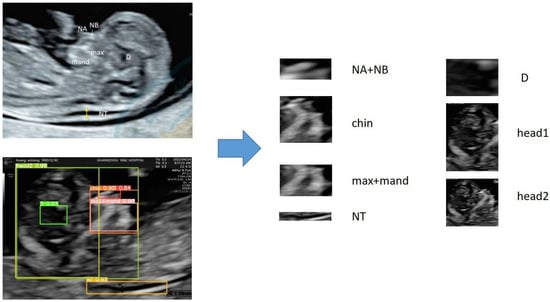

The examination section used in this study is the median sagittal section, which includes anatomical structures such as NT (nuchal translucency), NB (nasal bone), nasal tip, jawbone, and cranial crest, which are used in clinical diagnoses of high-risk fetuses [19,20]. Considering that the nasal tip, nasal bone, maxilla, and mandible have positional relationships, this study included them in the same region of interest. In addition, because the brain contains complex positional information, it is also considered a region of interest. Although the diencephalon is not related to screening for genetic disorders, it is an important anatomical structure in this section. Additionally, our study attempts to extract this anatomical structure to explore the feasibility of extracting key anatomical structures. In summary, this section divides the regions of interest that need to be extracted based on clinical diagnostic experience, and the detailed information is shown in Figure 1.

In Network A, the BiFPN feature fusion network and ECA attention mechanism are used to improve the YOLOv5 network, named YOLOv5 + BiFPN + ECA. After discussion with physicians and reference to clinical data, seven regions of interest in the ultrasound images were extracted, and they were named Chin, head1, head2, D, NA + NB, max + mand and NT.

Figure 1. Determination of regions of interest (ROI). NA + NB: apex nasi and nasal bone; NT: nuchal translucency; D: Diencephalon.